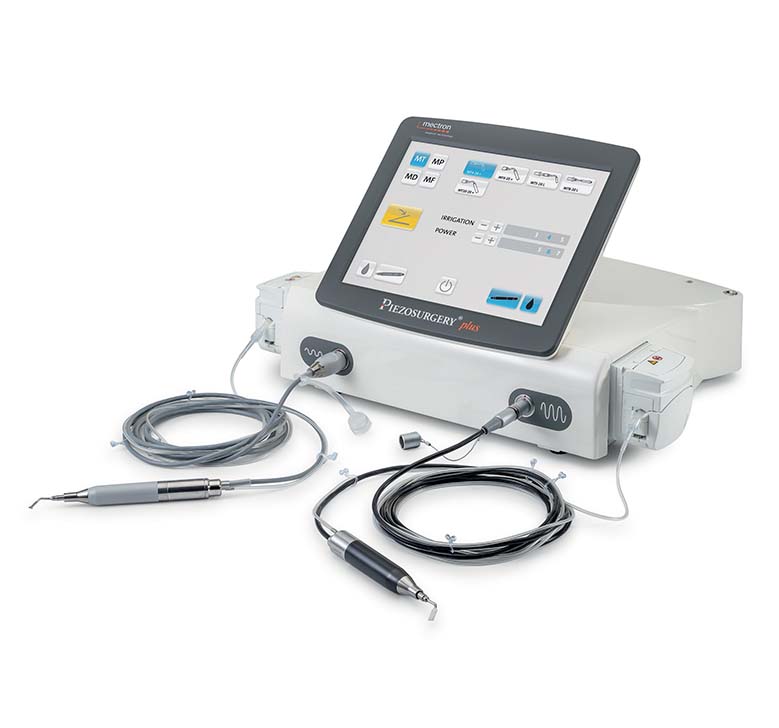

PIEZOSURGERY® plus

DESIGNED TO BE COMPLETE

PIEZOSURGERY® plus is the complete device: it is engineered to support an expansive range of surgical applications in Neurosurgery.

Unmatched efficiency, precision, and performance delivered through two independent handpieces and channels.